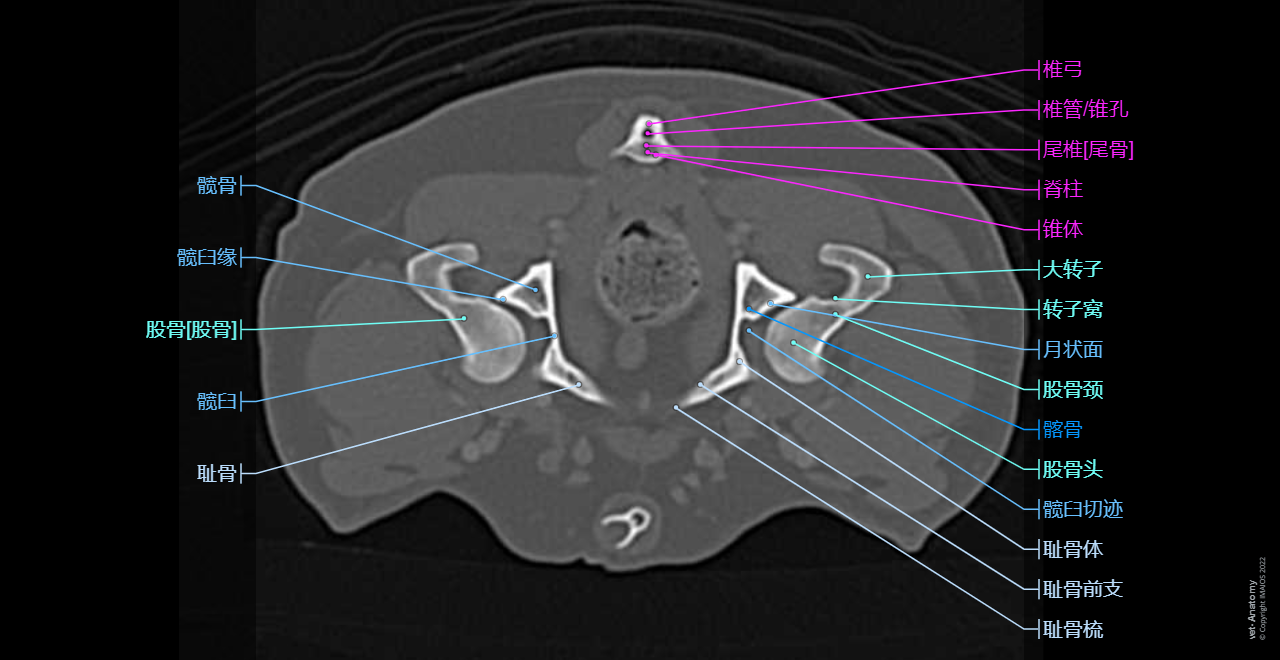

vet-Anatomy兽医图集的本模块是关于CT扫描的犬类腹部和骨盆。

CT图像来自一只健康的6岁阉割雄性犬。

在vet-Anatomy动物图集的此模块中,计算机断层扫描(CT)显示了标有解剖结构的犬科腹腔和骨盆横截面,并用3D图像显示犬科腹部。

CT图像存在3个平面方向(横向,矢状和背侧),并且使用两种对照方式(软组织/血管和骨骼)展现。本模块的末尾提供其他3D解剖图像,便于进一步了解犬科总体解剖结构,展示了骨骼、内脏(肝脏、脾脏、胰腺、消化道)、泌尿生殖系统、动脉、全身静脉系统(主要是尾腔静脉及其分支)、门静脉系统、肌肉和表面解剖的三维容积透视图。

Dog - Pelvis - Perineum - Anatomy

Dog - Coxal bone - Penile bone [Baculum]

Dog